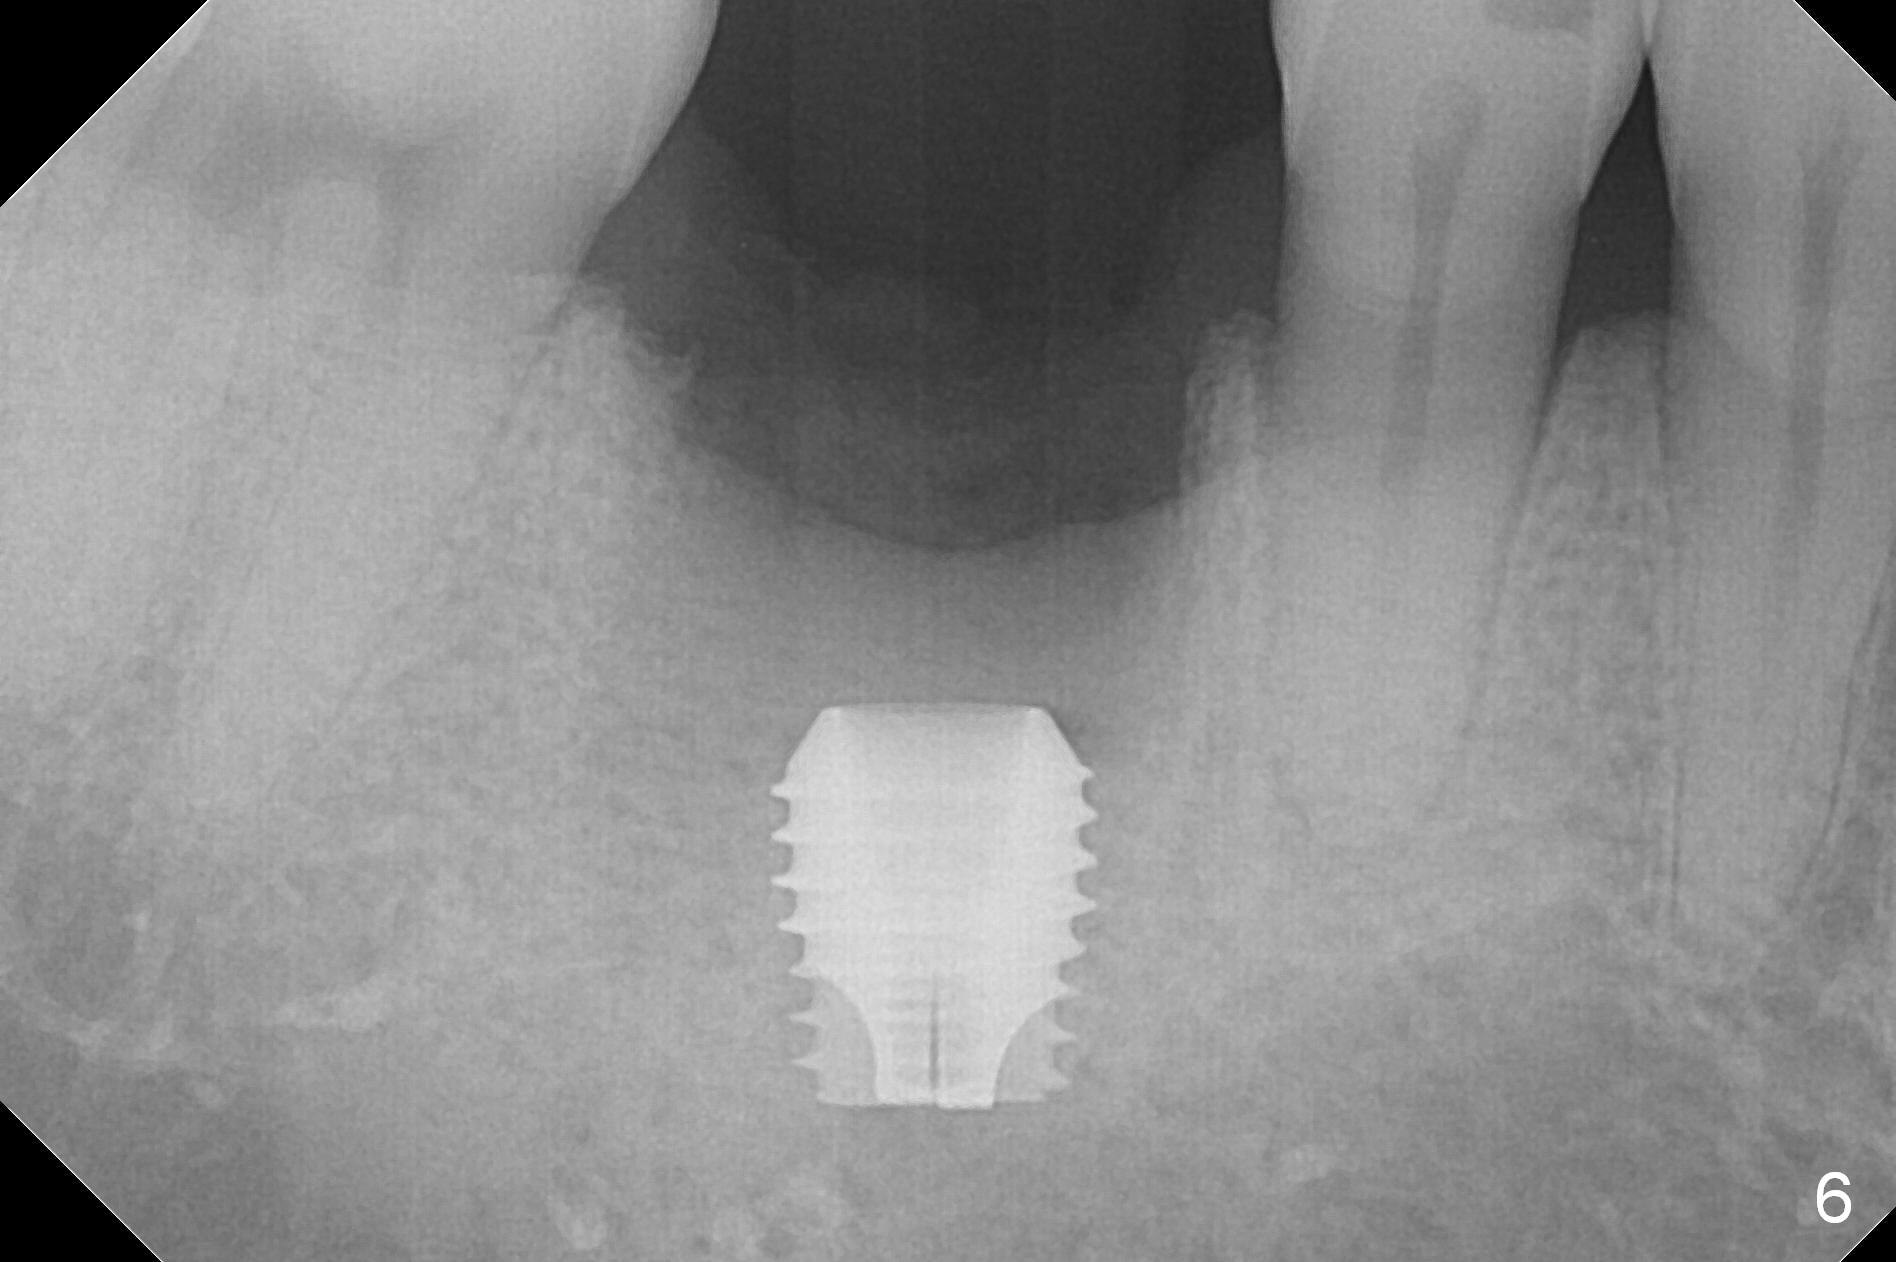

After extraction of the tooth #30 with Class V furcation involvement (Fig.1 (>),2 (L: lingual)), initial osteotomy depth is 8 mm with infiltration anesthesia, but a parallel pin is able to be inserted for 16 mm without pain (Fig.3). There is oozing from the osteotomy. Osteotomy increases in diameter with depth at 8 mm (Fig.4 (3.8 mm drill),5 (5.3 mm tap)). As the Inferior Alveolar Canal (IAC) is indistinct with increased pain during osteotomy, a 5.9x6 mm implant is placed with >50 Ncm following Septocaine infiltration (Fig.6). When bone graft (Fig.7 *) and 7.8x5.5(6) mm abutment (Fig.7,8) are placed, panoramic X-ray is taken (Fig.9). There appears to be a thick layer of spongy bone in the posterior mandible between the red and yellow dashed lines (Fig.5,9). Panoramic X-ray and/or CBCT should be taken if preop PA does not reveal IAC. This patient seems to be a bruxer. There are mandibular tori. Bone loss (furcation involvement) is not proportional to his oral hygiene status. Functional loading (progressive) should be delayed due to bruxism and the short implant.